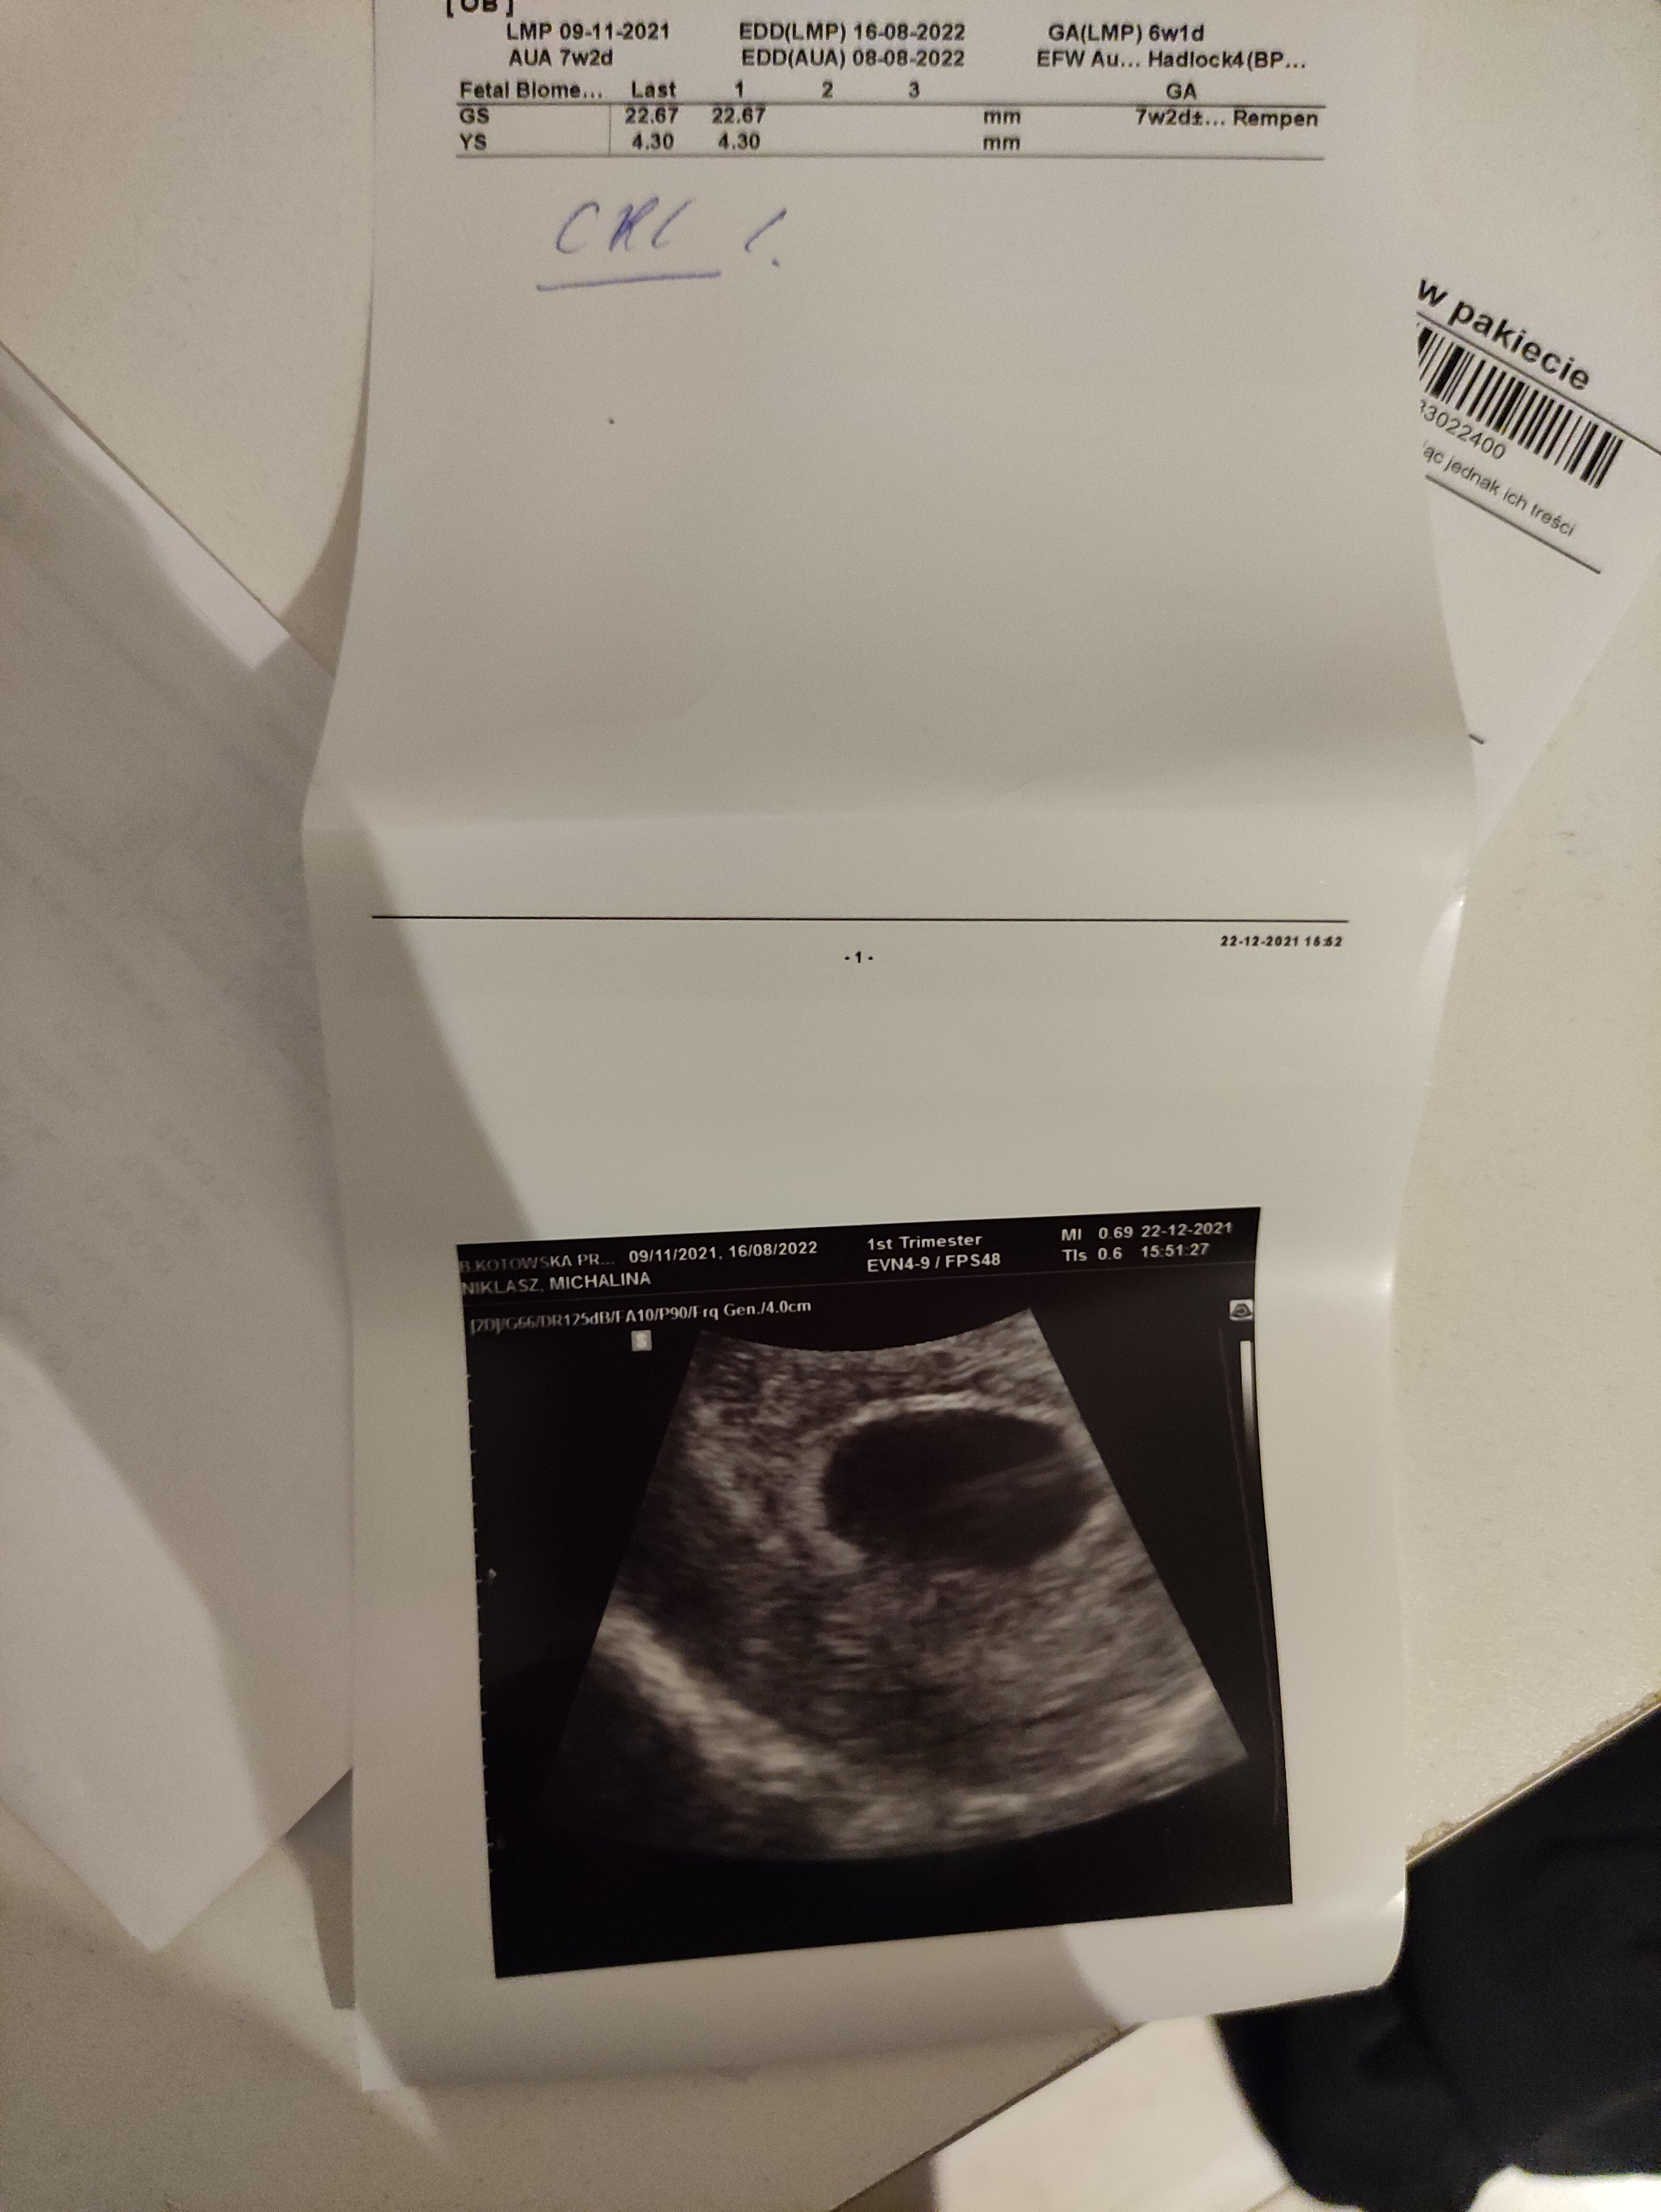

Jestem właśnie w 8 tygodniu od ostatniej miesiączki. Byłam w 6 tygodniu o był pęcherzyk ciazowy wraz z ciałkiem żółtym według opisu GS 22,67 mm a YS 4,30 mm ale bez serca po dwóch tygodniach czyli wczoraj byłam znowu u lekarza ale tym razem nie widział ciałka żółtego tylko pęcherzyk 21,04 mm bez serca. Stwierdził pusty jajo płodowe. Czy to możliwe i mogę liczyć jeszcze na cud ?

• IMG_20220106_161946.jpg

IMG_20220106_161946.jpg

2,1 MB · Wyświetleń: 838